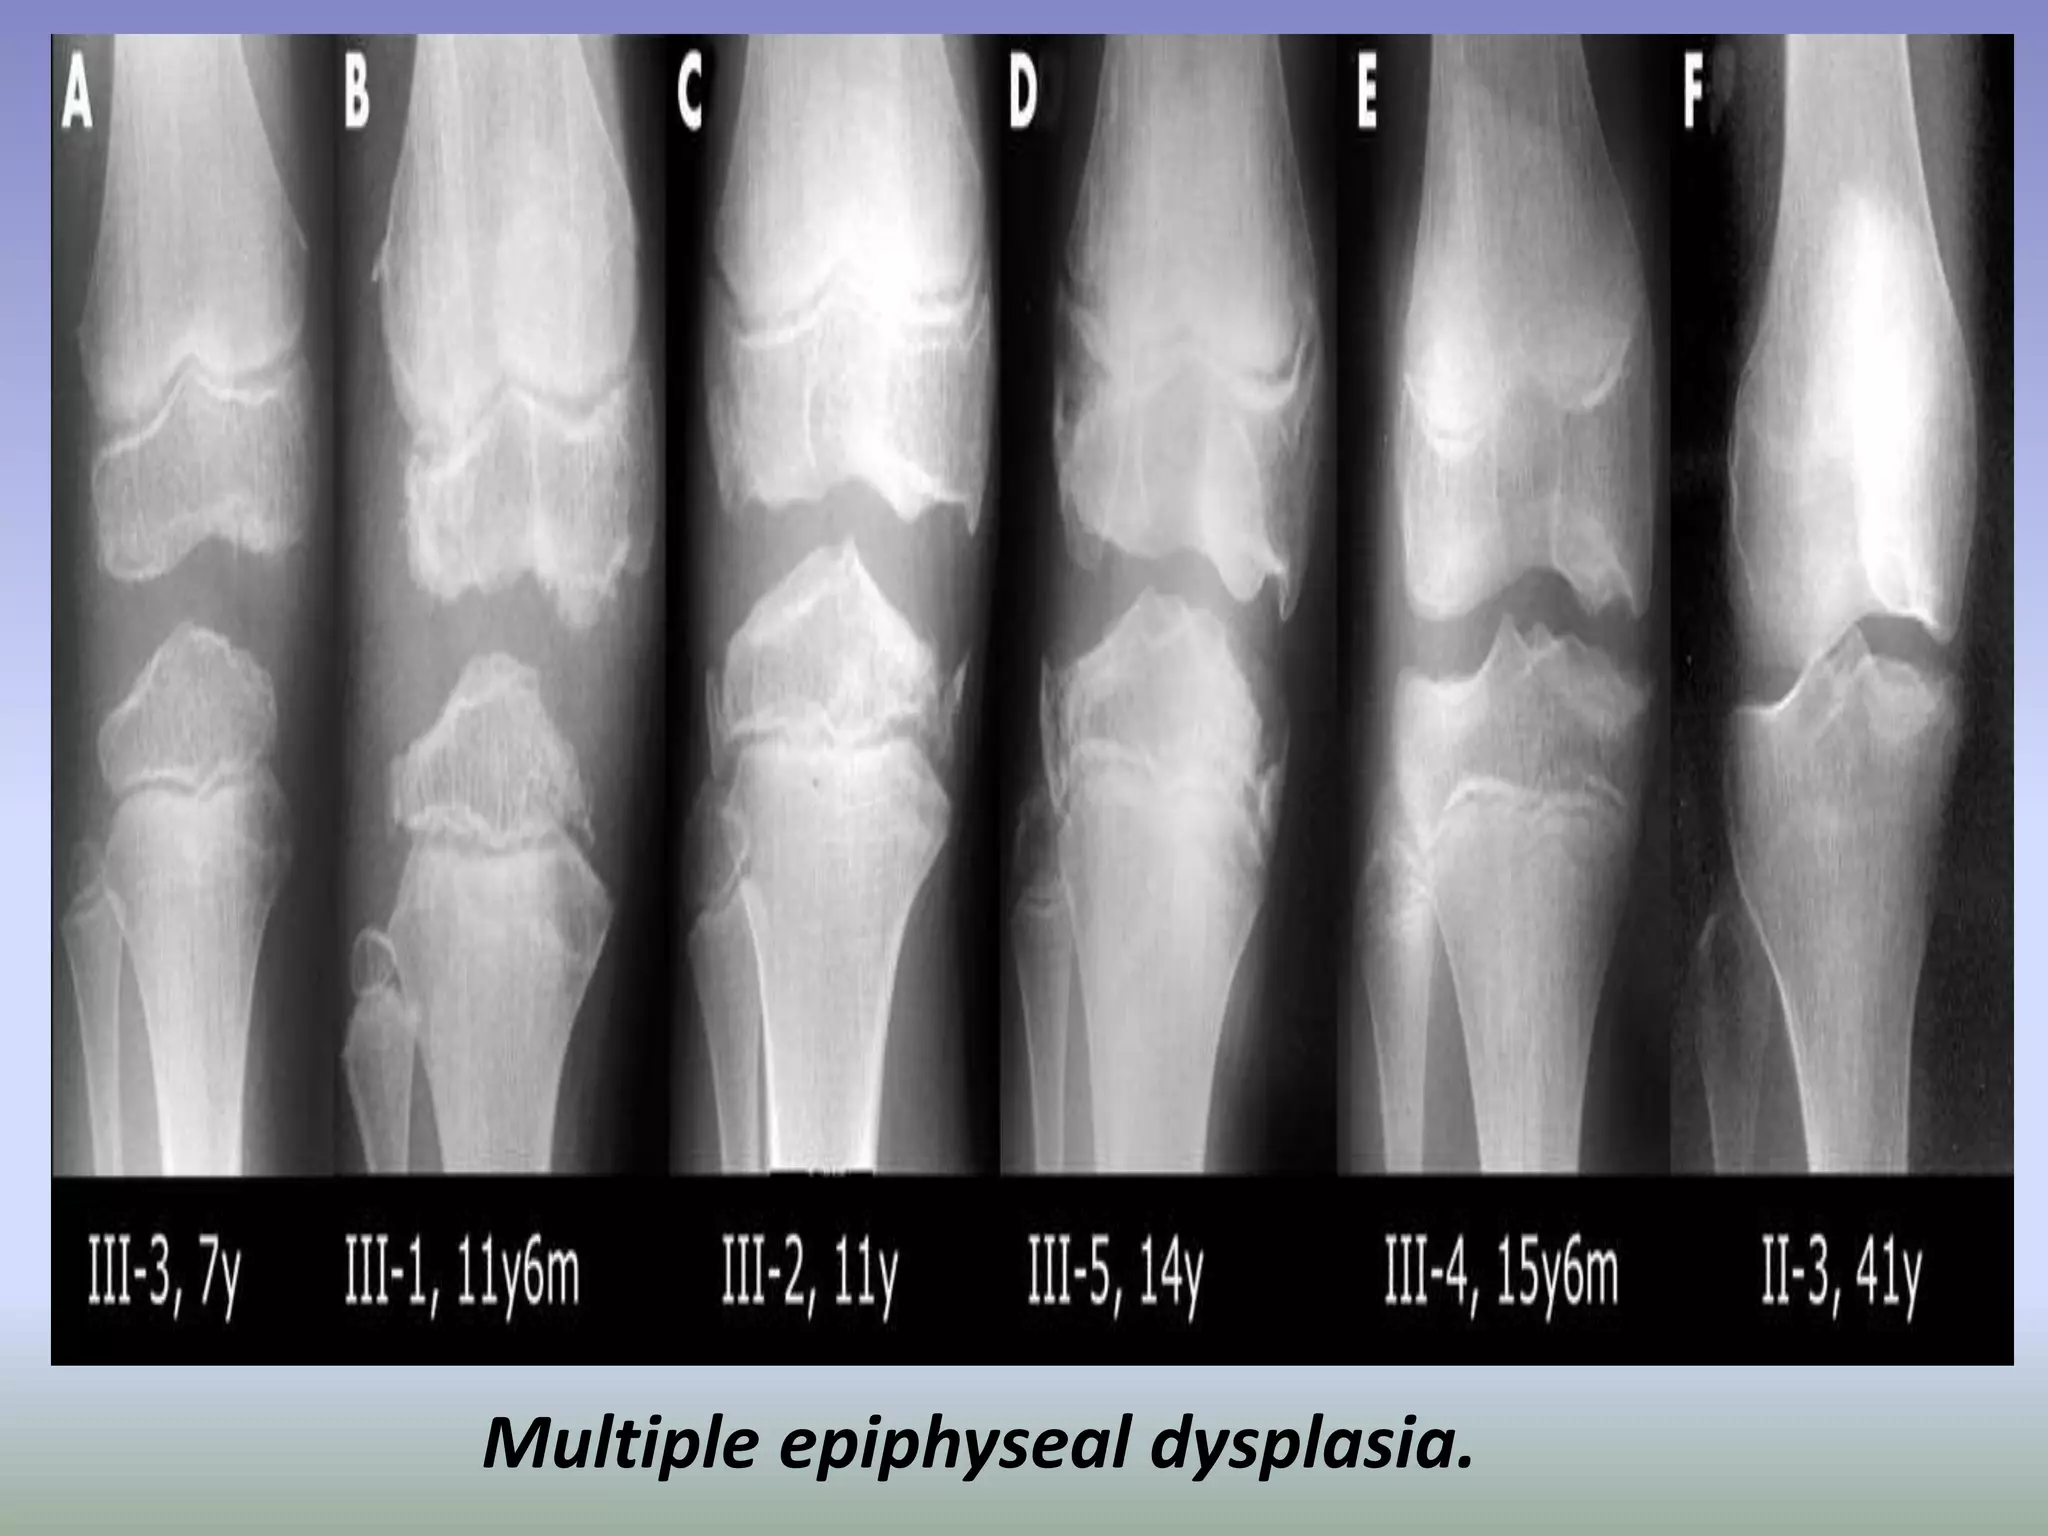

Multiple epiphyseal dysplasia.

Fairbanks disease or multiple epiphyseal dysplasia (MED) is a rare genetic disorder

(dominant form—1 in 10,000 births) which affects the growing ends of bones. Bones

usually elongate by a process that involves the depositing of cartilage at the ends of the

bones, called ossification. This cartilage then mineralizes and hardens to become bone. In

MED, this process is defective.

Multiple epiphyseal dysplasia (MED) encompasses a spectrum of skeletal disorders, most of

which are inherited in an autosomal dominant form. However, there is also an autosomal

recessive form.

Signs and Symptoms:

Children with autosomal dominant MED experience joint pain and fatigue after

exercising. Their x-rays show small and irregular ossifications centers, most

apparent in the hips and knees. A waddling gait may develop. Flat feet are very

common. The spine is normal but may have a few irregularities, such as scoliosis.

There are very small capital femoral epiphyses and hypoplastic, poorly formed

acetabular roofs. Knees have metaphyseal widening and irregularity while hands

have brachydactyly (short fingers) and proximal metacarpal rounding. By

adulthood, people with MED are of short stature or in the low range of normal

and have short limbs relative to their trunks. Frequently, movement becomes

limited at the major joints, especially at the elbows and hips. However, loose knee

and finger joints can occur. Signs of osteoarthritis usually begin in early adulthood.